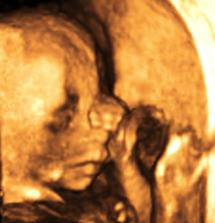

Ako nám to ide...